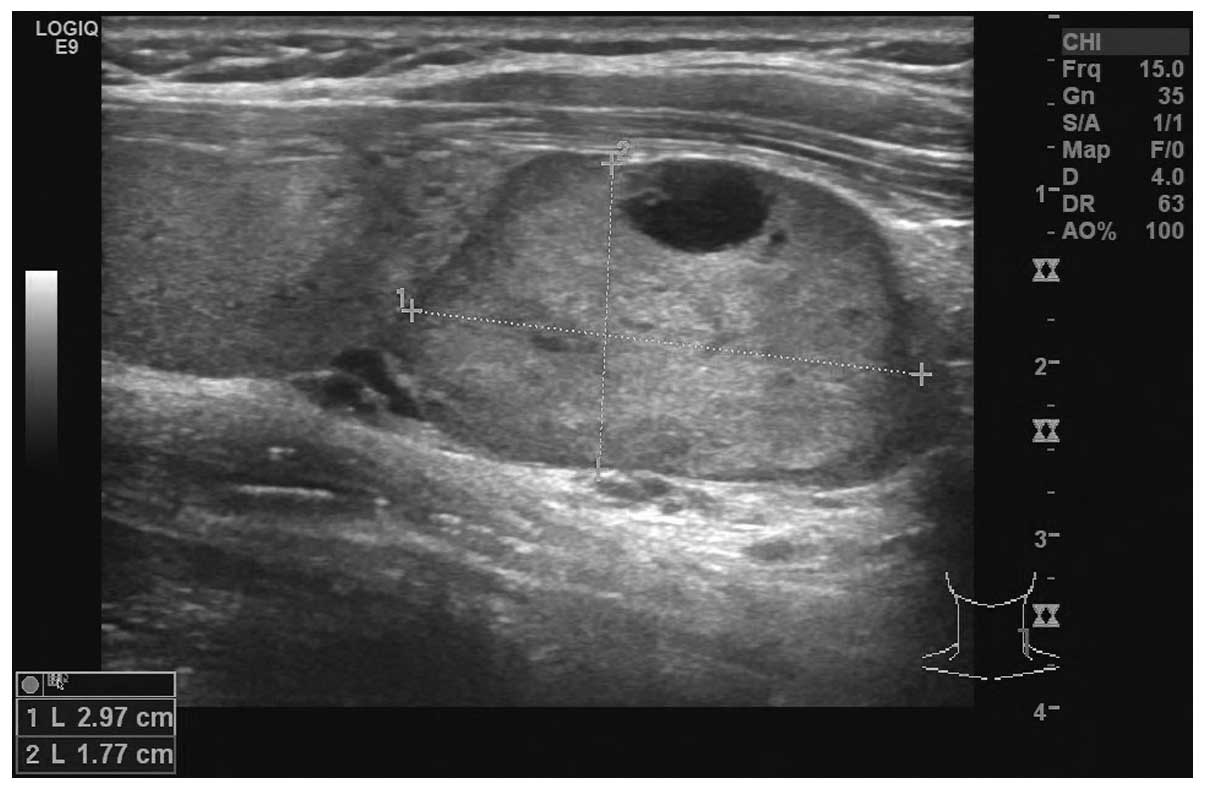

Figure 1.

Ultrasound image of a parathyroid adenoma.

Sensitivity and positive predictive values

Ultrasonographic examination of the neck revealed 92 cases of occupied lesions in the parathyroid gland and 10 cases in the thyroid gland (Fig. 1). The remaining 5 cases had normal neck ultrasonography results. The sensitivity and positive predictive values were 86.0% and 95.3%, respectively. Eighty-three patients underwent Tc-99 m sestamibi scanning. The accumulation of radioactivity was observed in 75 of these patients (Fig. 2). The sensitivity and positive predictive values were 90.4% and 94.1%. The combination of an ultrasound and 99 m Tc-sestamibi scan localized hyperfunctioning parathyroid in 76/82 patients (92.7%). The sensitivity in identifying parathyroid tumors by CT and MRI was 80.8% and 79.6%, respectively (Table I).